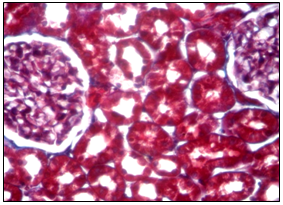

The following morphological changes were taken for statistical analysis: cell infiltration, interstitial edema, and interstitial fibrosis. For the analysis of morphological data, an estimated ball scale was used, described by Rodrigues-Iturbe (2005), where 0 is unchanged, 1 is weak, 2 is moderate and 3 is pronounced changes (Figure 1) & (Table 1).14 The program Statistica for Windows 6.0 was used for statistical processing of the obtained results with conducting correlation analysis. Significant differences were considered indicator sat p<0.05 (Figure 2). After dissection at 1 month of experiment, animals from Group 1 with VUR had kidneys of normal size, capsule was shiny, pyelocaliceal segments slightly widened, with mild hyperemia of the cortical parenchyma and perirenal cellular tissue. Histologically we observed moderate polymorphic-cell inflammatory lymphoplasmacytic infiltration (Figure 3 (A)), slightly extended convoluted tubules, glomeruli were in most cases stored (Figure 3 (B), mild interstitial edema, and focal capillary hyperemia (Figure 3 (C). Minimal processes of sclerosis were revealed in the cortical area of ​​the capsule of some glomerules and in glomerular basement membrane in convoluted periglomerular tubules (Figure 3 (D).

Figure 2 Microscopic aspect of the kidney of a rat from the control group at 6 months. Cortical zone of the kidney parenchyma, Mason aniline blue coloration about 20 oc. ten.

Figure 3 Microscopic changes in an individual from Group 1 with VUR at 1 month of the study. Painting of Van Gies on (A) x100, in Mason (B, D) x100.